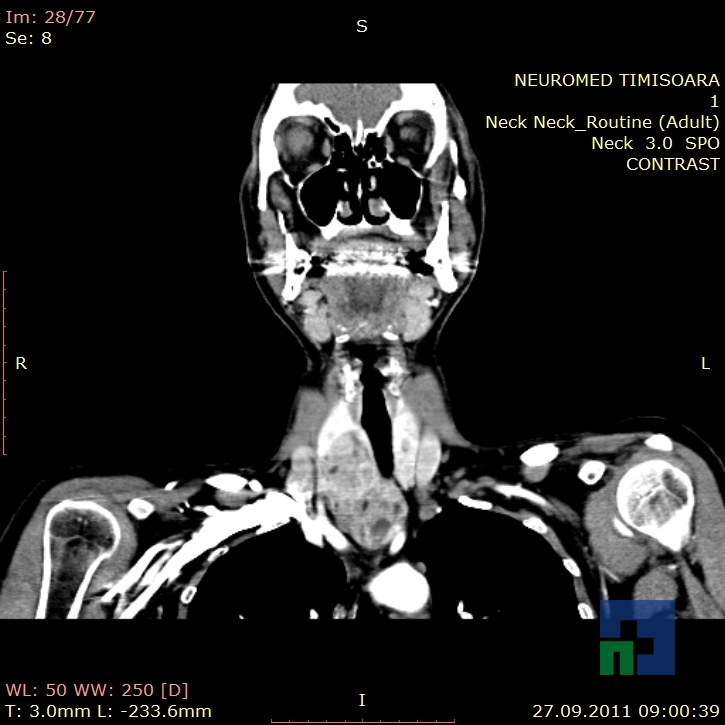

Examinare de rutină cerebrală, nativ și cu substanță de contrast (SDC) pentru diagnosticul:

- Accidentelor vasculare cerebrale ischemice sau hemoragice

- Tumorilor cerebrale